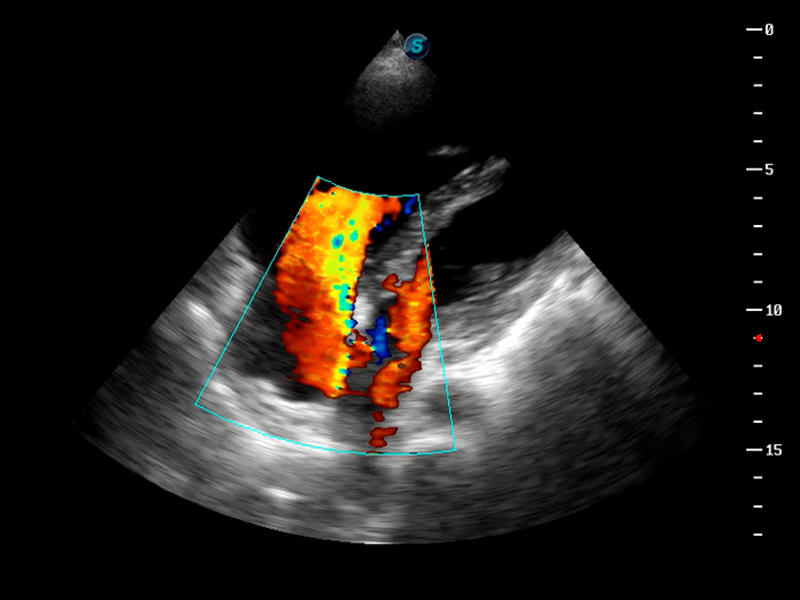

S9便携式彩色多普勒超声诊断仪是诸侯快讯官网研发的高端便携彩超设备,外观设计新颖、产品性能卓越。S9在便携超声领域采用了突破传统的触摸屏交互设计,并以先进的软件硬件技术和设计理念,为您带来清晰的图像质量、稳定的工作性能和便捷的操作体验。

TDI组织多普勒成像